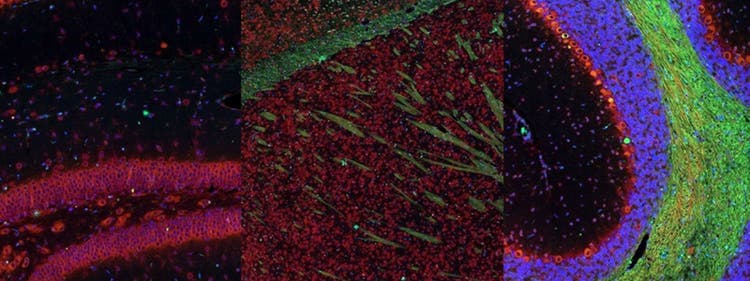

Fluorescence imaging of a mouse brain

Aunque todas estas imágenes parecen distintas en un primer plano, todas componen una única imagen de un cerebro de ratón capturada con el procesamiento de imágenes por fluorescencia.

El científico británico Sir George G. Stokes observó por primera vez que la fluorita mineral mostraba fluorescencia al iluminarla con luz ultravioleta y acuñó la palabra "fluorescencia". Stokes descubrió que la luz de fluorescencia tiene longitudes de onda más largas que la luz de excitación, un fenómeno conocido como cambio de Stokes. La microscopía por fluorescencia es un método excelente para estudiar materiales que pueden fluorecer en su forma natural (calificado como primaria o autofluorescencia) o cuando se tratan con químicos que puedan fluorecer (conocido como fluorescencia secundaria).